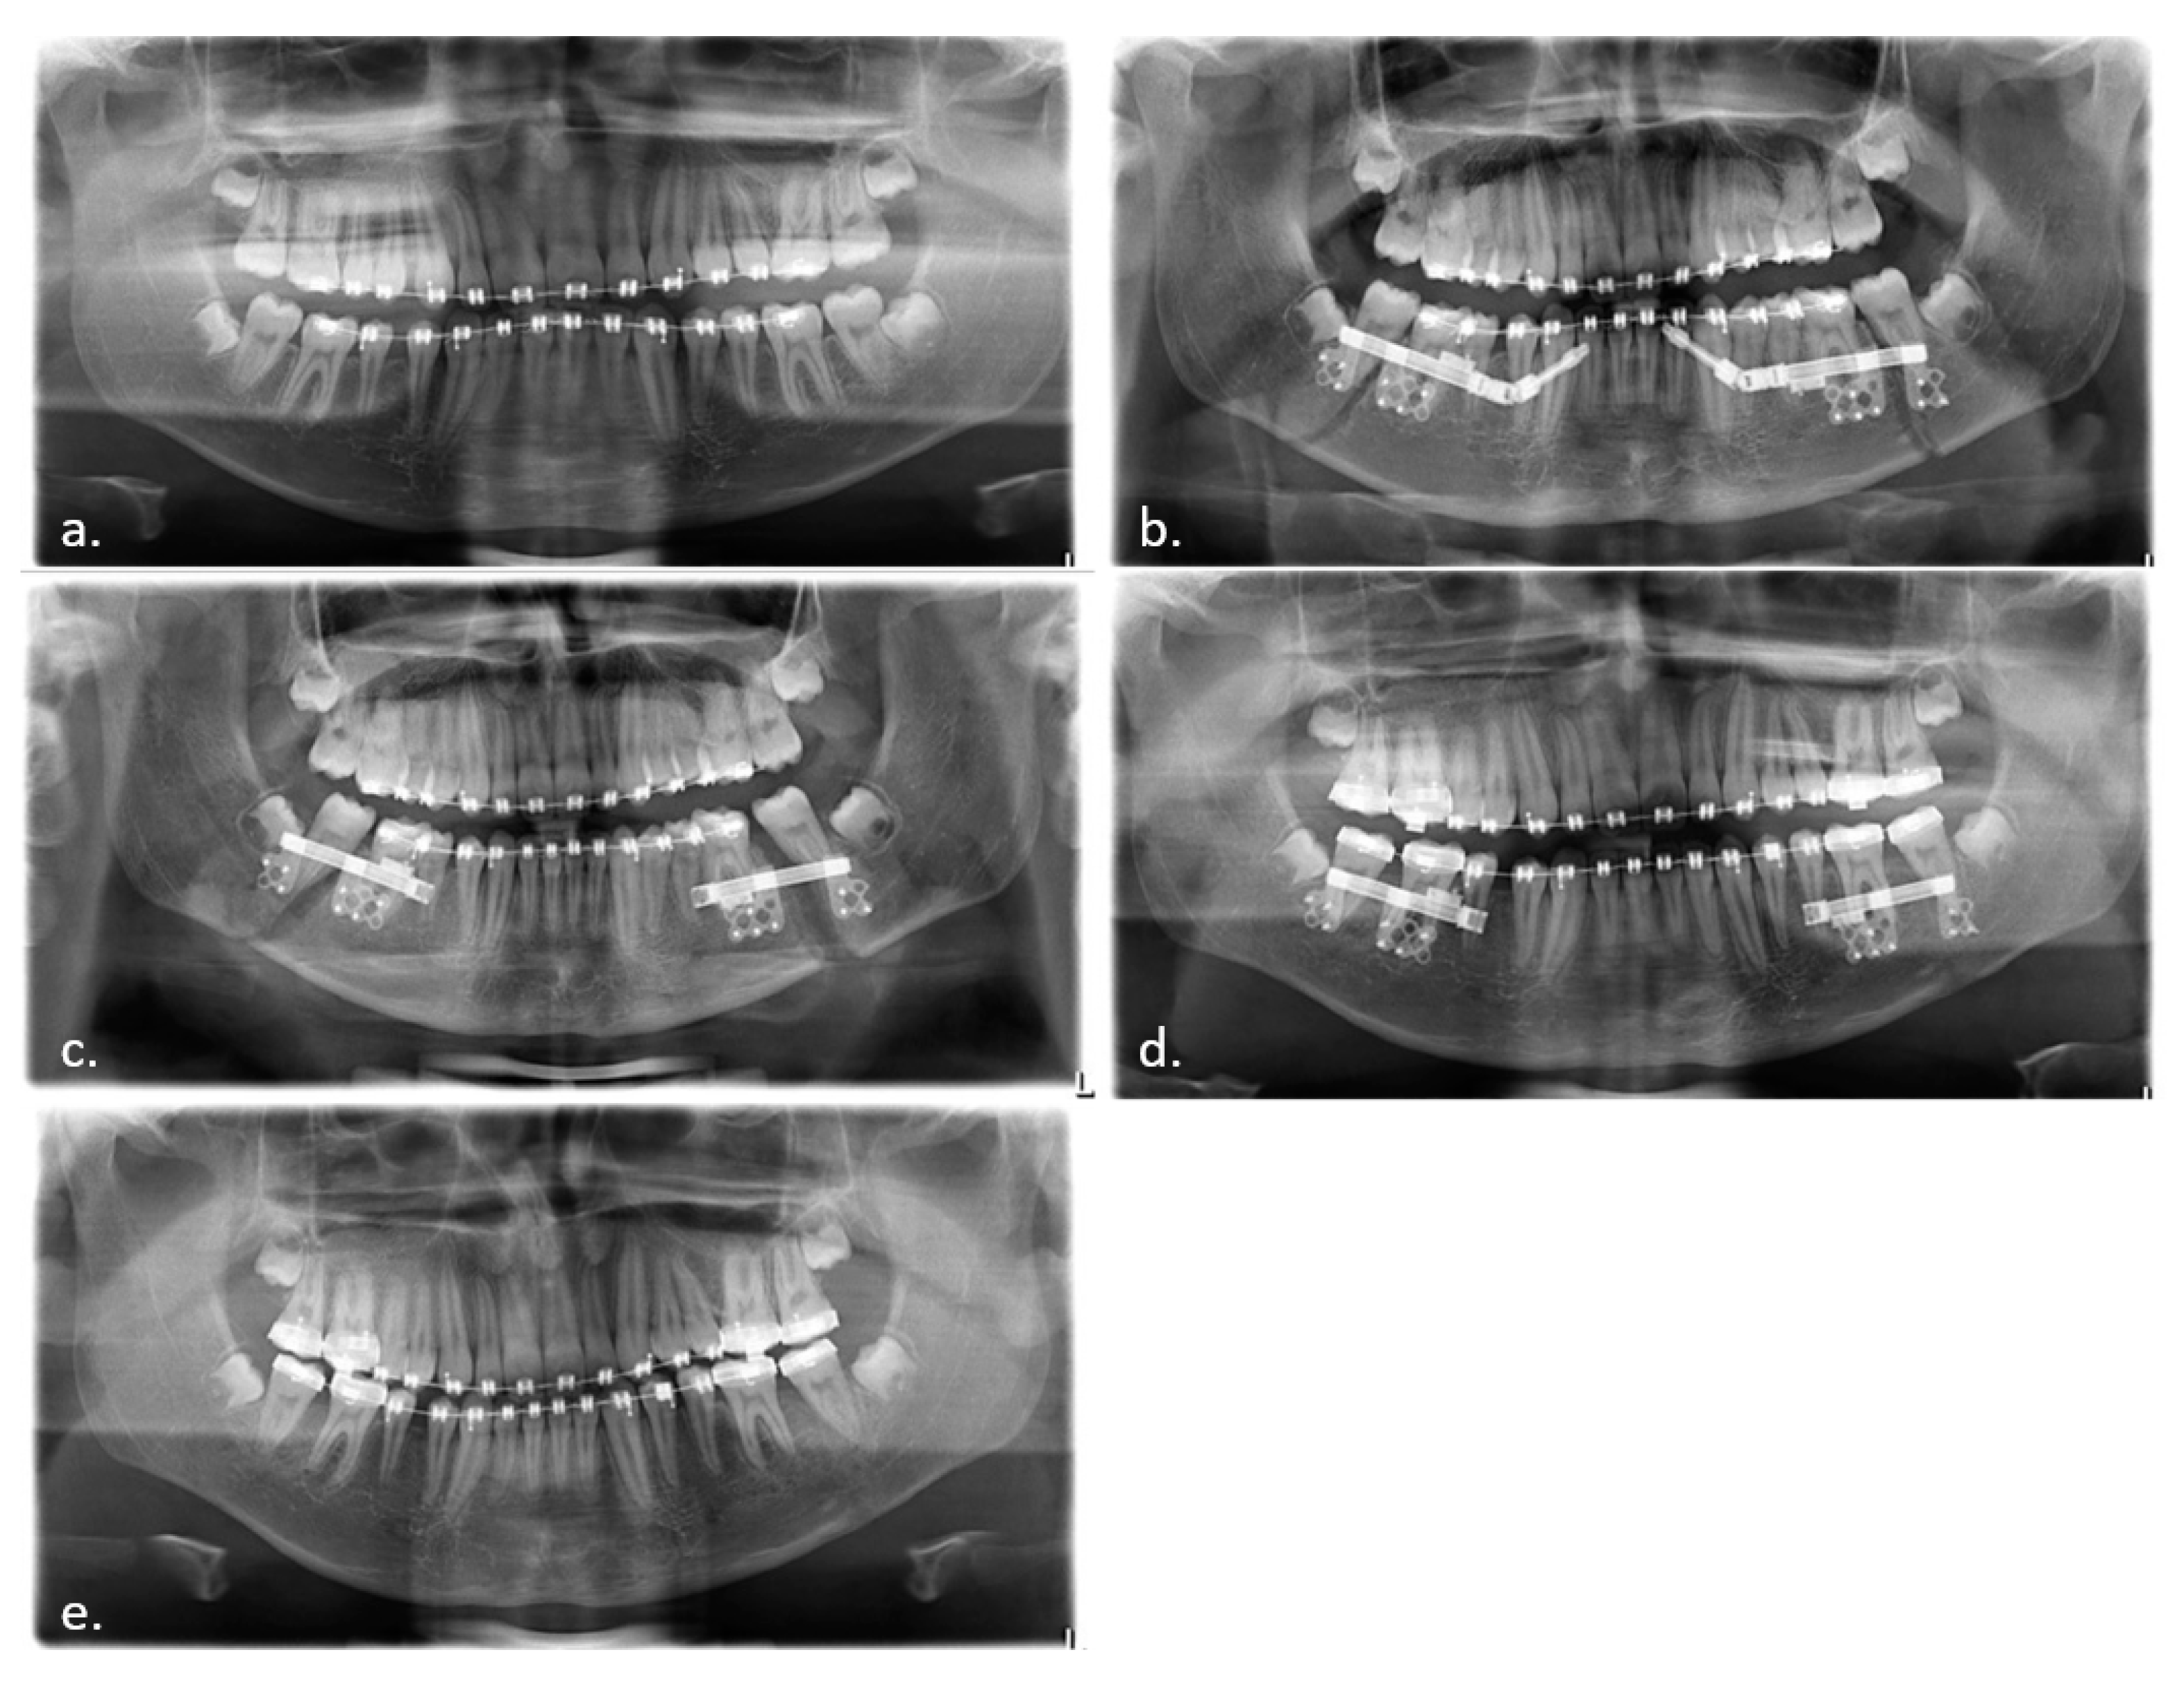

Like any distraction treatment, IMDO is a dynamic procedure that requires regular radiological and clinical monitoring (Figure 3, Figure 4 and Figure 5).

Figure 3.

Radiological follow-up. Panoramic X-rays: (a) Before IMDO. Note the small diastema between the first and second molars of the mandible. (b) Control after distractor placement. Note the symmetrical axis tilt of the distractors. (c) End of active distraction treatment and removal of activation rods for more patient comfort. (d) Bone consolidation 10 weeks after end of distractor activation. (e) After removal of the distractors.